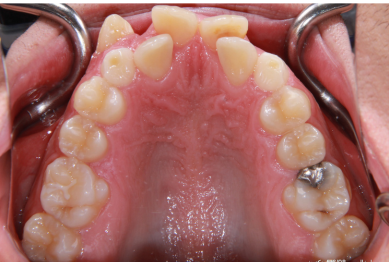

-  دندان ها روی هم قرار گرفته اند کج و نامرتب هستند. . زمانی رخ می دهد که فضای کافی برای رشد و نمو طبیعی دندان های دائمی وجود نداشته باشد.

-  دندان های نهفته (که به طور جزئی یا کامل در استخوان فک شما گیر کرده اند).

-  بین دندانها فاصله است